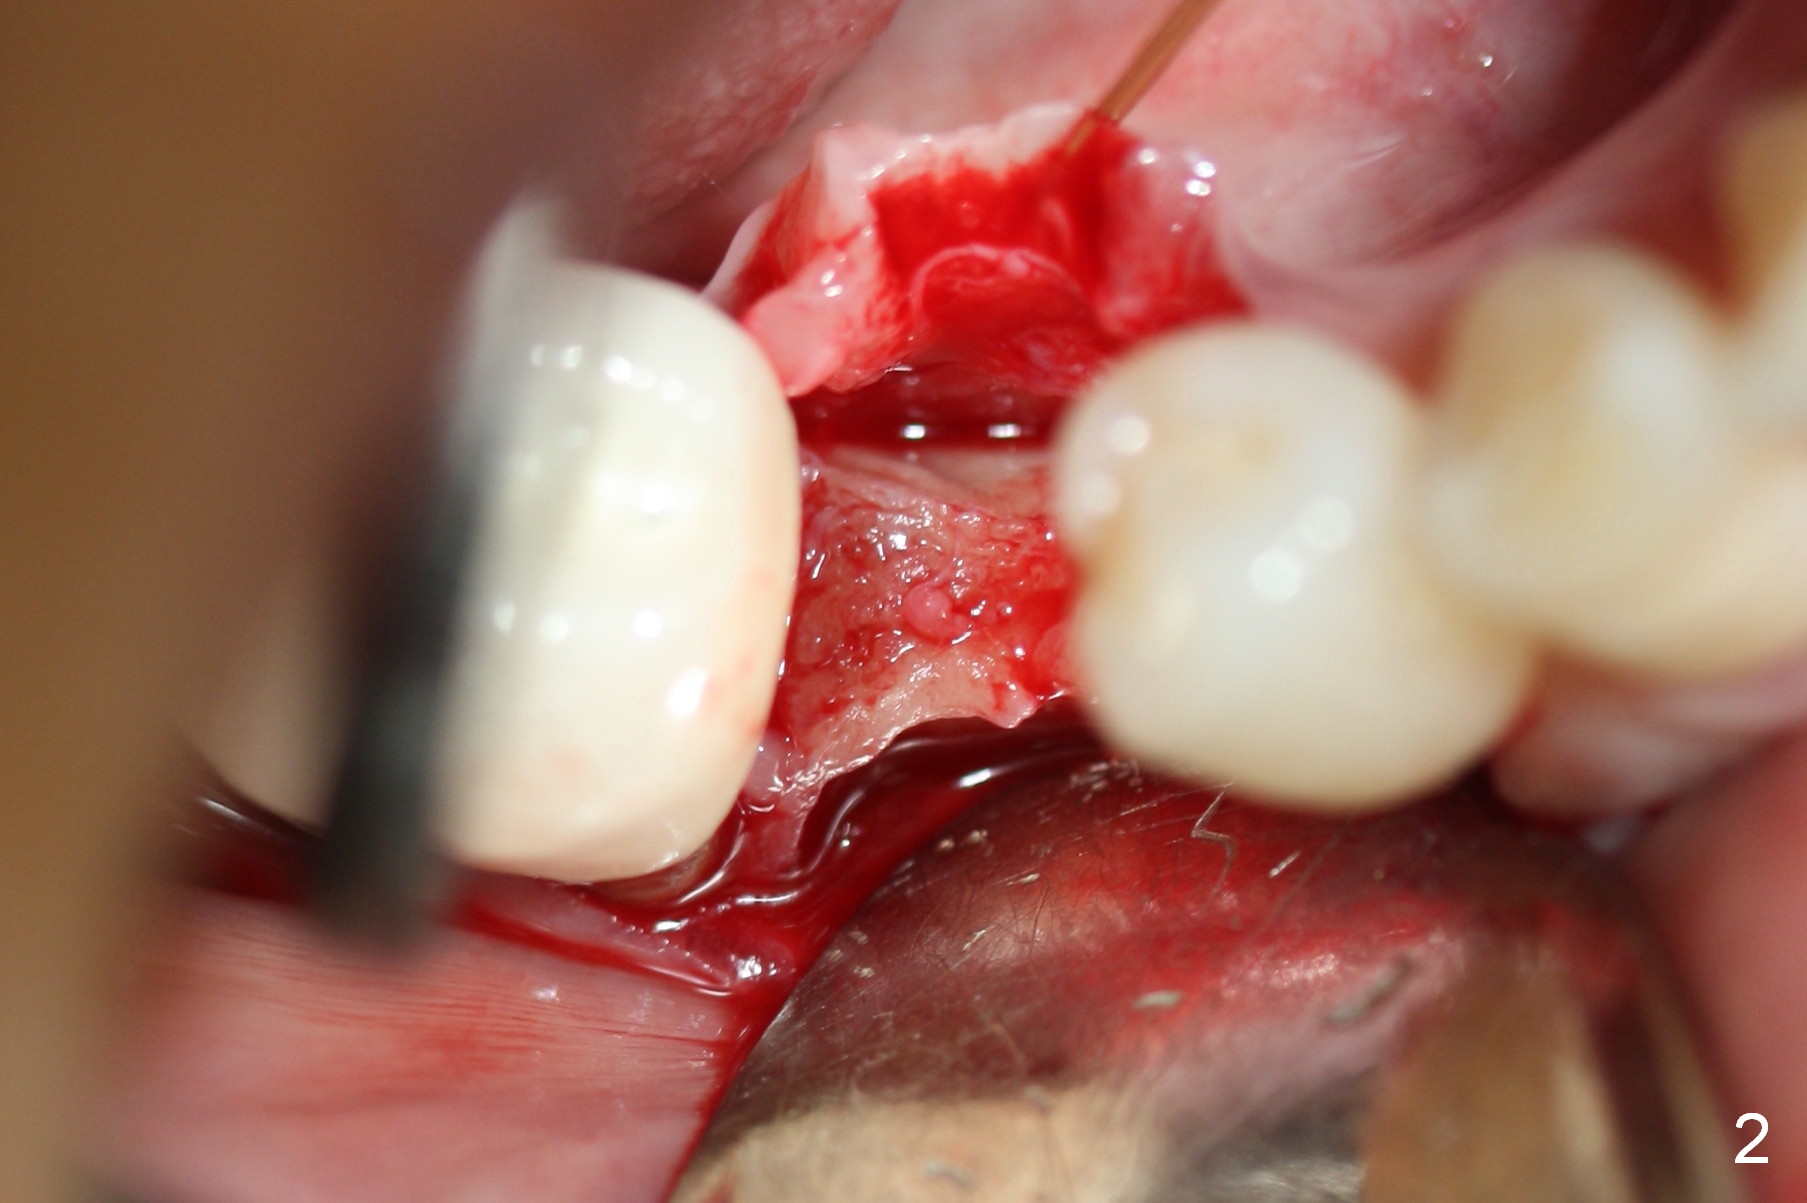

Preop photo shows the distal inclination of the tooth #28 (Fig.1). The distal surface of the latter is reduced before incision for implant placement at #29 (Fig.2). The buccolingual width is approximately 4 mm, as compared to 3 mm implant positioner (Fig.3). After 1.2x10 mm osteotomy (Fig.5), the mesiodistal cortical bone is removed with a small high-speed fissural bur (Fig.4). When a 2.5x12(2) mm 1-piece implant is placed (Fig.6), there is no buccal (Fig.7) or lingual plate perforation. There is no postop paresthesia. There is mild bone loss distal 4 months postop (Fig.8 *). Take photos before and after permanent crown cementation to show increase in ridge width after bone graft and improvement in gingival health after provisional modification. Take PA and/or BW post cementation to show that the distal bone resorption (Fig.8 *) is partially due to angulation. No continuous bone loss 15 months post cementation (Fig.9). There is mild bone resorption mesially 2 years 3 months post cementation (Fig.10). The soft and hard tissues remain healthy 4 years 3 months post cementation (Fig.11,12).